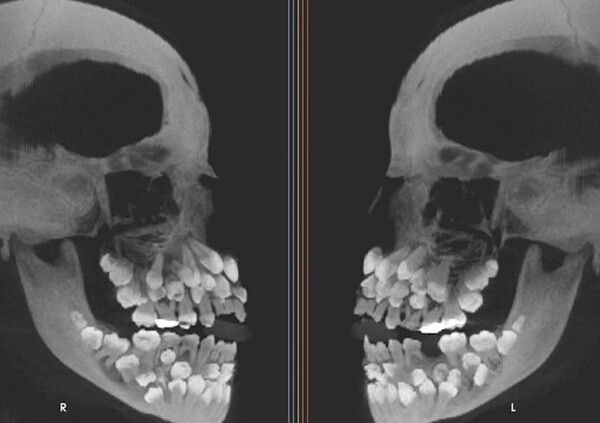

브라질에서 11세 소녀의 입 안에서 81개의 치아가 발견되는 전례 없는 희귀 사례가 보고됐다.

A양은 유치 18개, 영구치 32개, 과잉치 31개, 총 81개의 치아를 가지고 있었다.

의료진은 CT 검사를 통해 다발성 과치증과 흔히 동반되는 구개열, 쇄골두개 이형성증, 가드너 증후군 같은 질환은 나타나지 않았다고 전했다.

브라질 미나스제라이스주 후이즈데포라 연방대학 의사들은 "다발성 과치증의 경우 대부분 치아가 1~2개 더 많지만, A양처럼 유전적 증후군이 없는데 과잉 치아가 31개 발견된 것은 전례가 없다"고 말했다.

이 소녀는 수 많은 과잉치로 인해 치료에도 어려움을 겪고 있다. 과잉치 발치 시에는 턱 뼈 손상을 야기할 수 있기에 신중히 접근해야 하고, 잇몸 밖으로 드러나지 않은 치아도 있어 진짜 치아와 과잉치를 구분하는 일도 쉽지 않다.